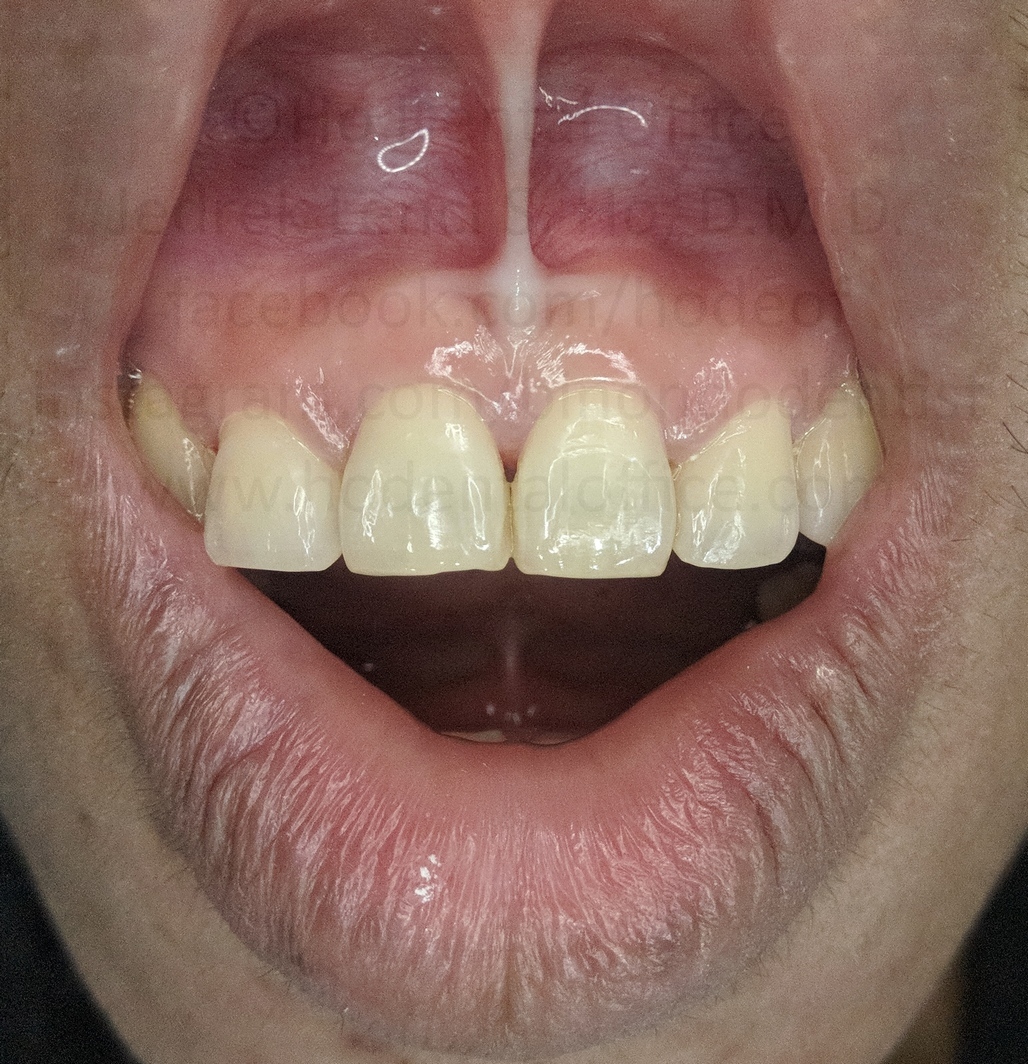

Patient came in for prophylaxis and orthodontic consultation on March 2017. Her chief complaint was the big gap in the middle of her two incisors.

Upon observation, a very big frenum attachment is evident, with the "pull" of the muscle fibers (seen while stretching the lips) reaching all the way up to the incisive papilla on the back of the upper incisors. Patient was also checked with x-ray to ascertain presence of impacted teeth, if any.

Since the cause of the diastema (big gap in the middle) was determined to be not caused by a hidden impacted tooth, it is highly likely that the strong frenum muscle attachment was the one causing it, as there have been documented cases similar to this that can be seen on dental textbooks and scientific papers.